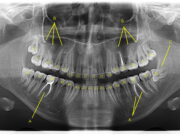

Для чего нужна ортопантомограмма ?

Ортопантомограмма - это своеобразный панорамный снимок челюсти. Именно он позволяет четко и точно оценить костную структуру челюсти, также выявить все возможные дефекты включая кисты,...